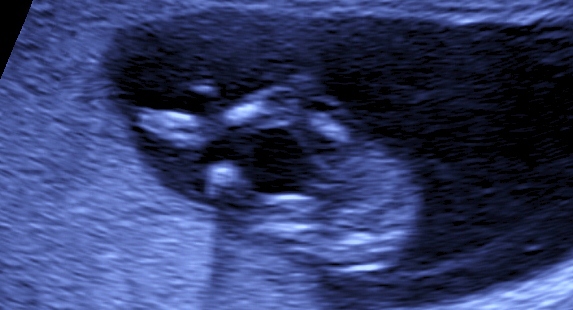

based on potty shot 100% :DD:

11 weeks is a bit early, potty shots unreliable and sorry but i cant see a nub in the profile shot. Do you have any other pics?